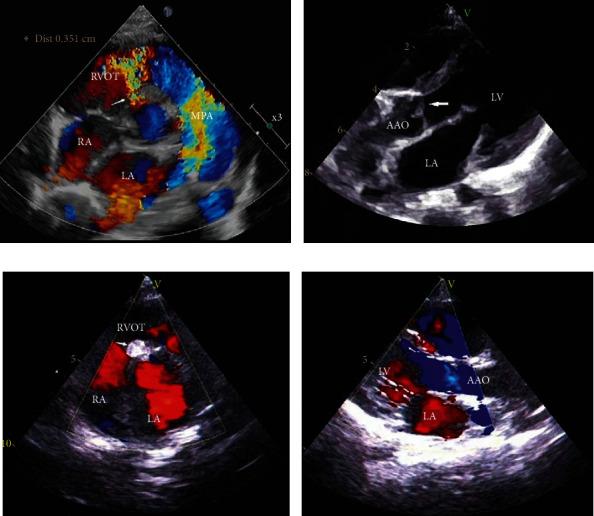

With the rapid development of transcatheter techniques and instruments, transcatheter occlusion for patients with perimembranous ventricular septal defect (pVSD) and aortic valve prolapse (AVP) was constantly being tried, while the efficacy and safety of pVSD with AVP remain controversial.

We retrospectively analyzed 164 children with pVSD and AVP who underwent transcatheter occlusion between January 2013 and November 2014. AVP was divided into 3 degrees according to right coronary leaflet morphology at end-diastole during aortic root angiography. Patient demographic and clinical data were collected.

There were 97 males and 67 females (median age, 40.0 (30.0-62.7) months; average weight, 16.94 ± 9.02 kg). Mild ( = 63), moderate ( = 89), and severe ( = 12) AVP success rates were 93.7%, 89.9%, and 58.3%, respectively. Immediately after procedure, there was no new-onset aortic regurgitation (AR) above trivial degree, residual shunt above mild degree, or complications requiring medication or operation, except for 1 patient who developed transient complete atrioventricular block. During follow-up, 1 mild AVP patient aggravated from mild to moderate AR and 1 moderate AVP patient aggravated from trivial to moderate AR. The new-onset AR in mild, moderate, and severe AVP was 2%, 1.8%, and 20%, respectively. AR disappeared in 17 patients. Residual shunt occurred in 9 patients after procedure, 4 of which disappeared during the follow-up period. No serious complications occurred in any patient during follow-up. Five-year cardiovascular event-free survival rates for mild, moderate, and severe AVP were 89.6%, 94.5%, and 80.0%, respectively.

Transcatheter occlusion of pVSD with mild and moderate AVP has a high success rate and few complications, which is safe and effective in long-term follow-up. Transcatheter occlusion of pVSD with severe AVP has low success rates and high AR incidence. Therefore, transcatheter occlusion of pVSD with AVP is recommended for mild to moderate, but not severe, AVP.